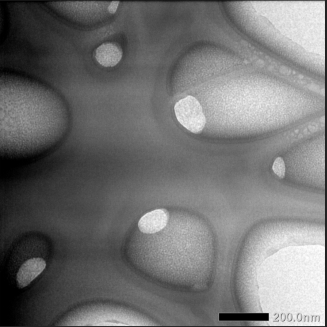

Characterization NLCs honey extract optimal formula with transmission electron microscopy (TEM)

TEM evaluation aims to look at microstructural analysis, defect identification, interface analysis, crystal structure, atomic arrangement in crystals, and nanometer-scale elemental analysis.

Fig. 6: TEM NLCs honey extract optimal formula. The magnifications are 40.000 x

Morphological tests are needed in NLC characterization, which aims to determine the shape and internal structure of NLC, which already contains active drug ingredients. Lipid crystals generally have a non-spherical platelet shape. The non-spherical shape of lipid nanoparticles has advantages, namely affecting NLC stability, entrapment efficiency (EE), drug loading, drug location in the NLC, and drug release rate, having a large surface area, short diffusion path, and low lipid layer compared to the non-spherical shape of lipid nanoparticles. Round requires more surfactant to stabilize the NLC [19]. This follows the NLCs of optimal formula honey with a high surfactant composition, namely 25.96. This morphology test can also determine the particle size of an NLC. The particle size determined by TEM was shown to be smaller than that determined by dynamic laser light scattering techniques. Based on observations, it was obtained that the NLCs of the optimal formula honey had separate particles, no lumps, oval shape, and smooth and uniform size, ranging from 100 nm to 200 nm. The optimal formula for honey NLCs was obtained using the high-pressure homogenization method.